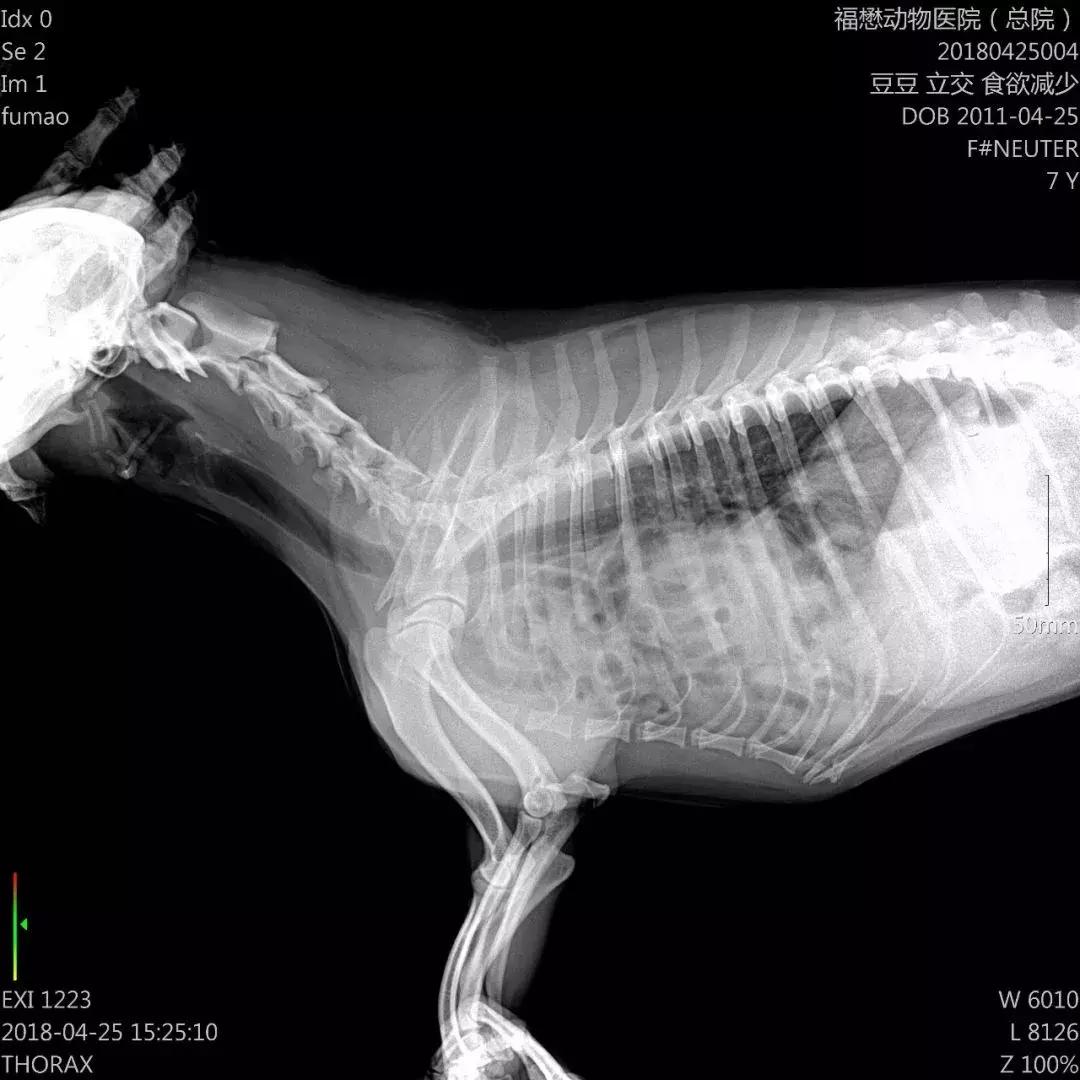

☝豆豆胸片

我们天河分院接待了豆豆,很不幸,检查过程中发现豆豆得了膈疝,腹腔的内脏器官肠道以及胃部分肝脏进入胸腔,压迫心肺,肝受损;皮肤以及黏膜黄染。